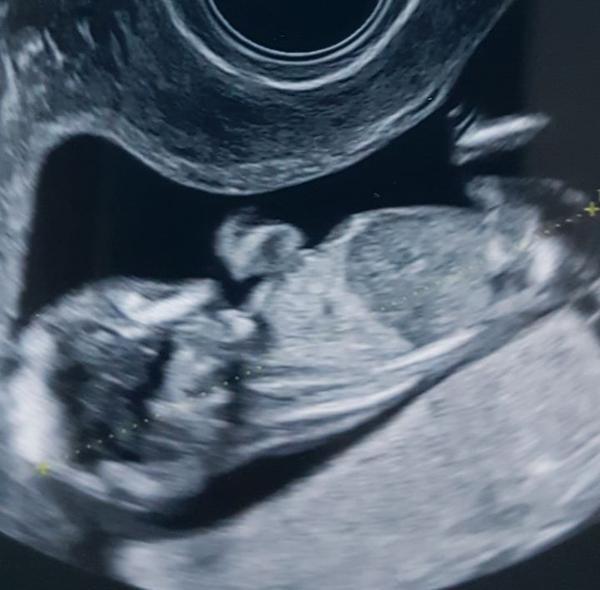

Ahojte 😊 tipnete si prosím pohlaví? Fotka je z 12+2 😊

@allisenka🙂 chlapeček

Ještě tu mám jednu fotku 😃

@almidrob2539 Dík za tip 😃 mám už dva kluky a myslela jsem si že by to mohla být konečně holka. Jinak budeme mít dohromady 5 kluků 🤦♀️😃 oba kluci na utz vypadali úplně jinak